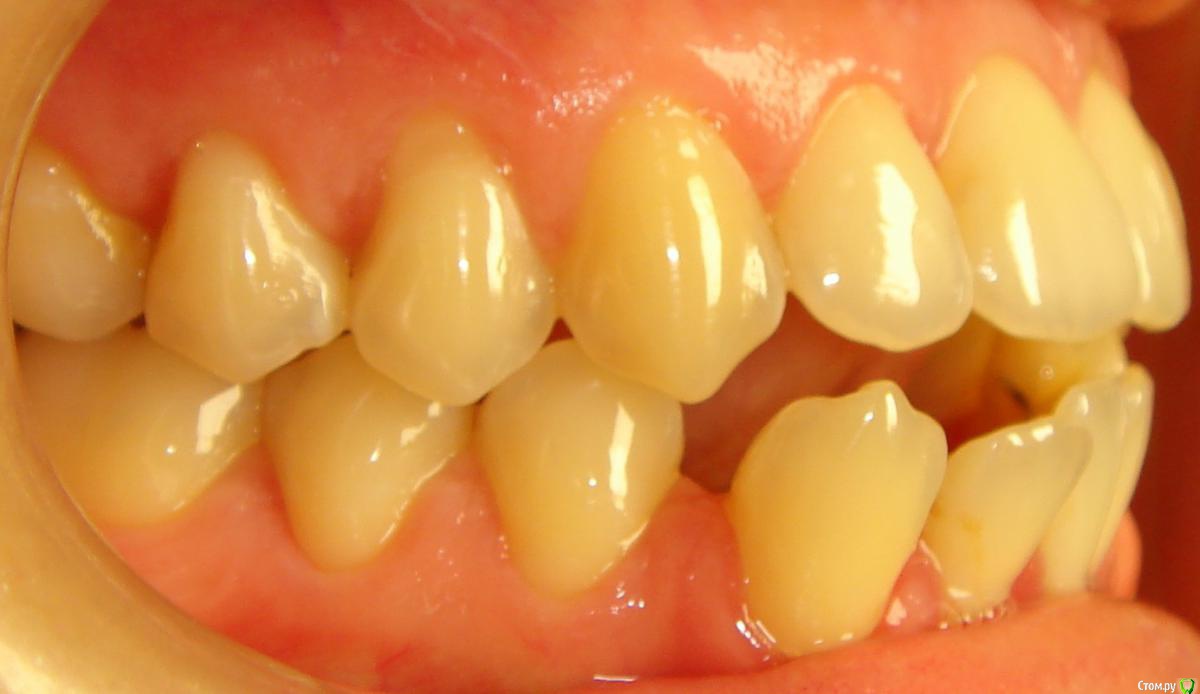

Opdihatop Опубликовано 4 марта, 2017 Поделиться Опубликовано 4 марта, 2017 И снова здравствуйте, коллеги. Вот такой вот случай к рассмотрению. Много лет назад пациентка уже проходила "камуфляжное" лечение. Со слов пациентки оно было закончено с передним открытым прикусом. Сейчас ситуация такая. Пациентка думает над ортохирургией, но меня смущает фронт н/ч. И по снимкам и по ситуации во рту корни 32, 31, 42, 43 зубов фенестрировали лингвальную кортикалку почти на всем протяжении, 33 - вестибулярную. Вопрос вот в чем: что делатьс этими зубами? Возможно ли их поставить на место? Или лучше не трогать, дольше простоят? Ссылка на комментарий

Opdihatop Опубликовано 29 мая, 2017 Автор Поделиться Опубликовано 29 мая, 2017 Как? Очень просто, "ДОЛЕЧИВАТЬ"! Тут фенестрация произошла из-за невылеченного инфантильного типа глотания и очень качественного (тут без сарказма) несъемного ретейнера. Исправь прошлый доктор язык, или поставь ретейнер хуже, так чтобы он его давление не выдержал и сломался, было бы все иначе. Ссылка на комментарий